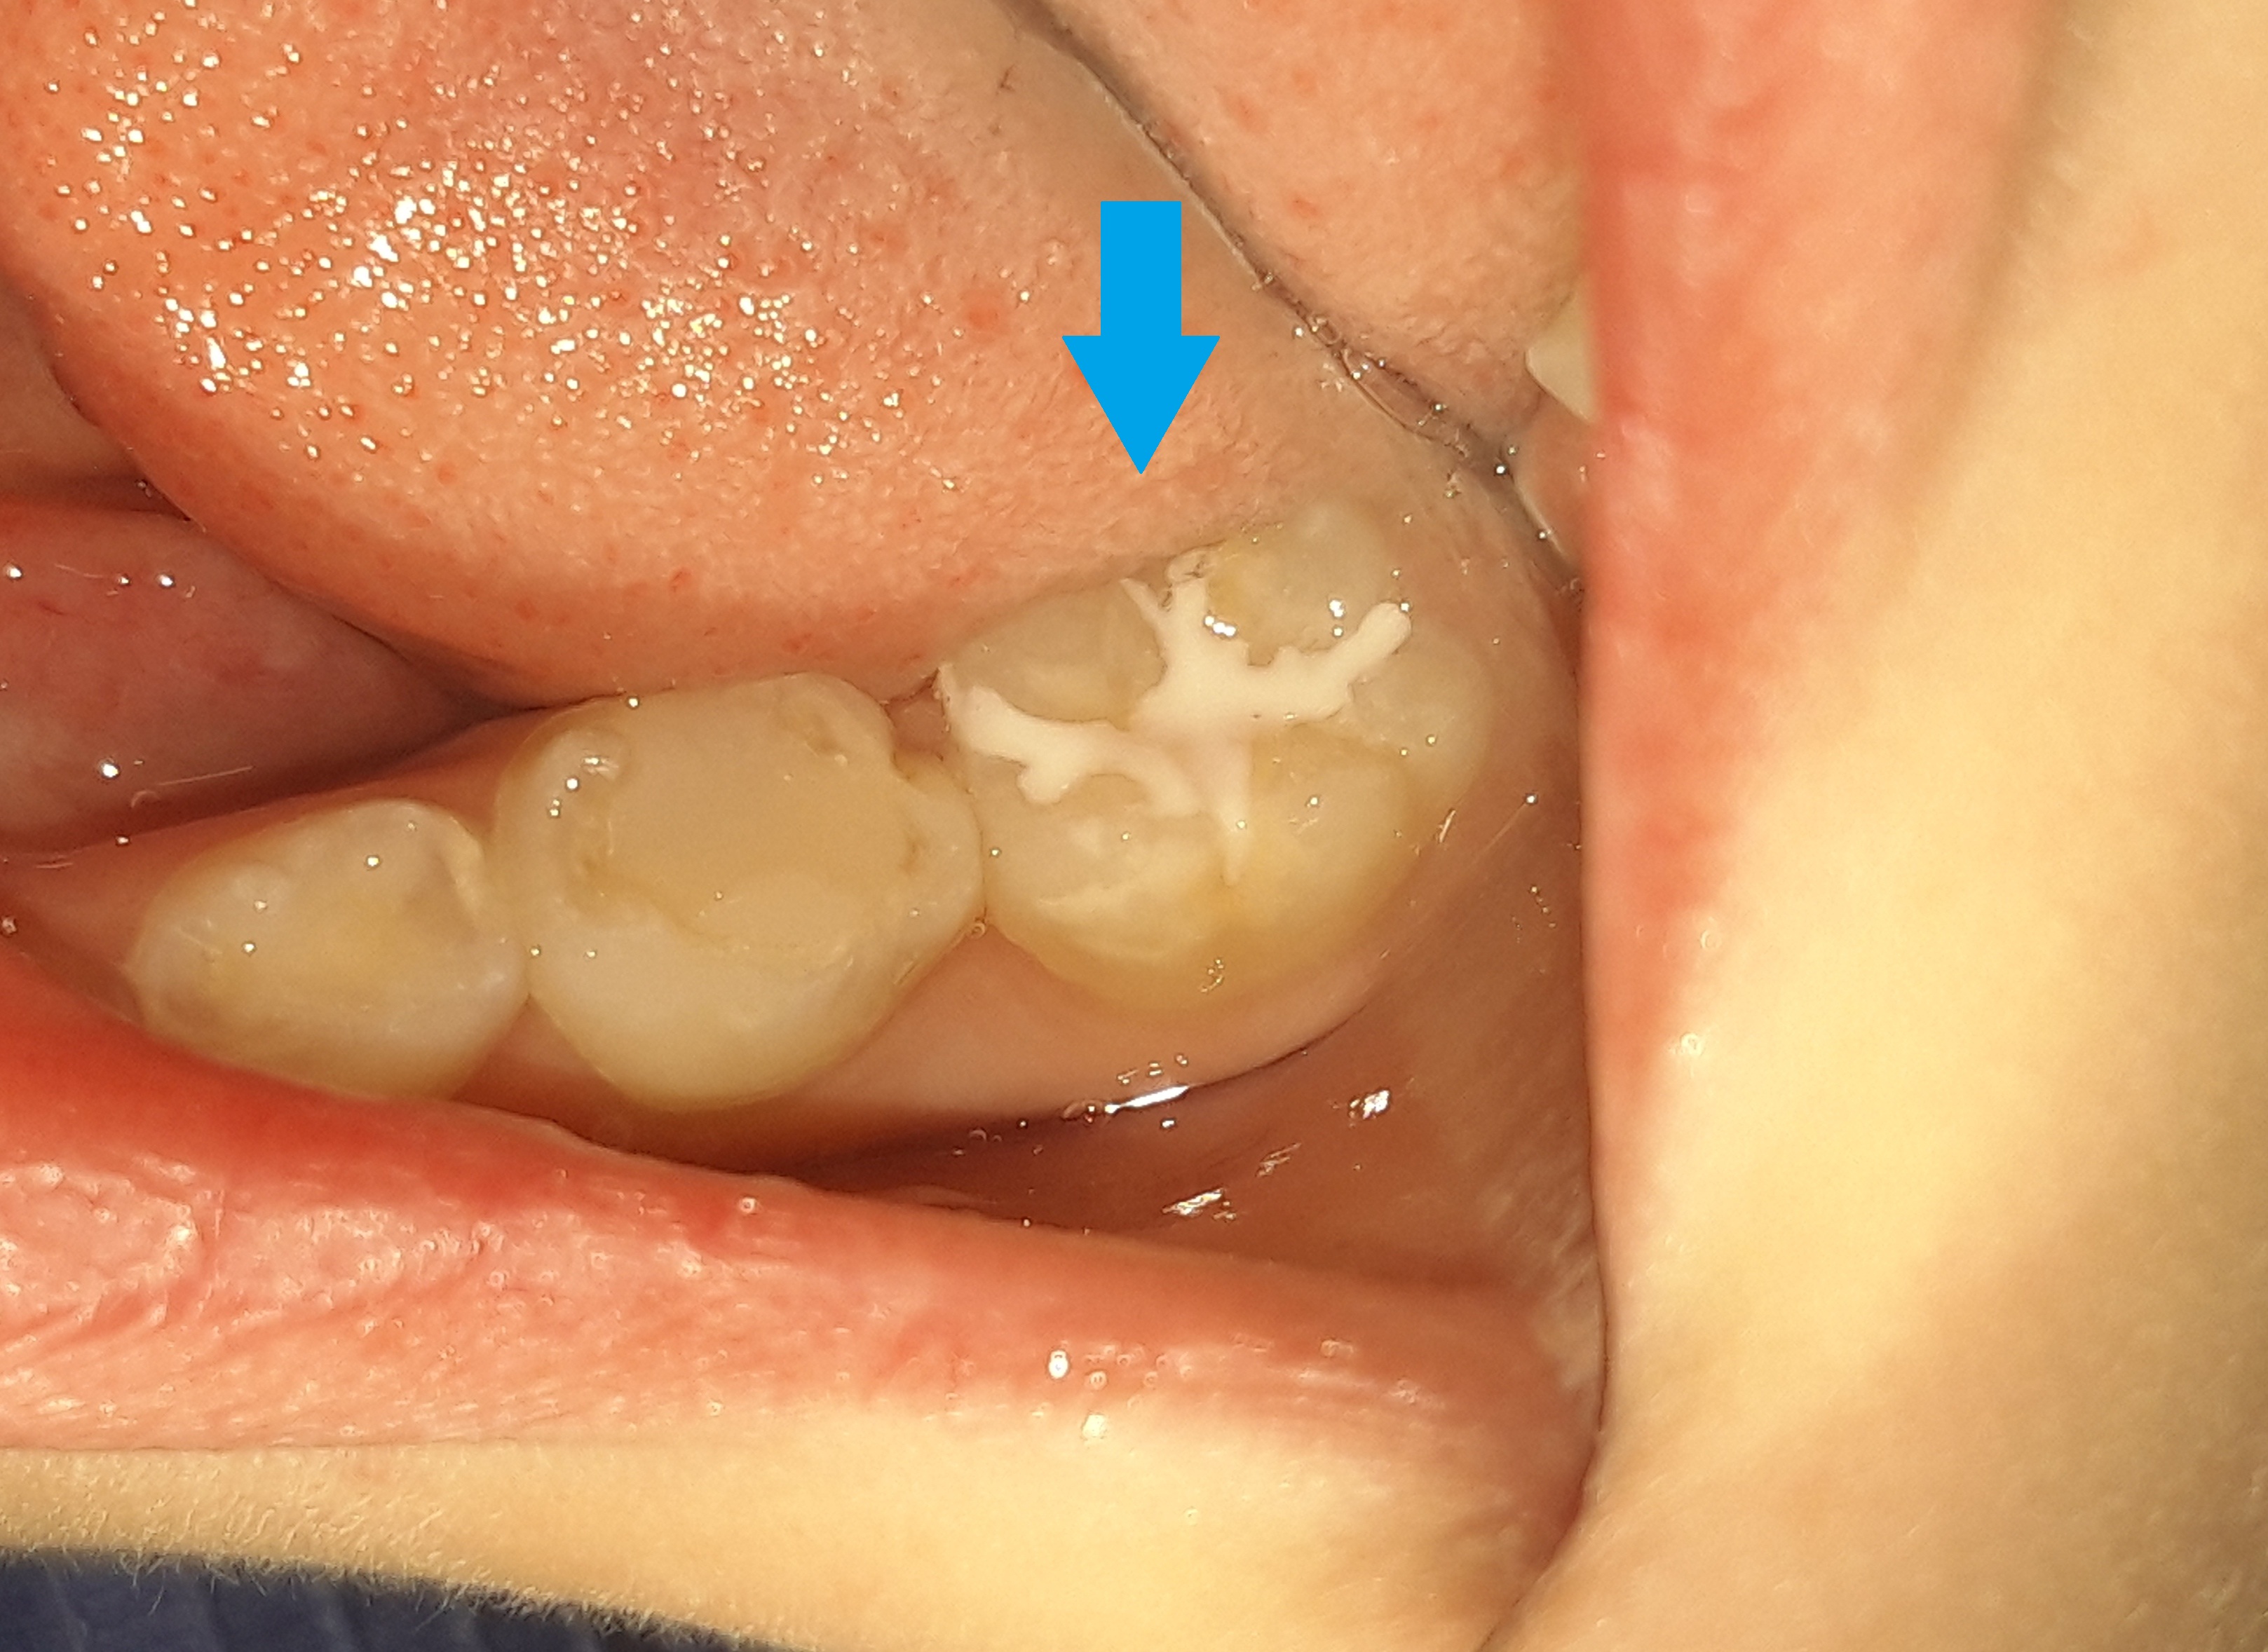

Στο αγόρι αυτό τοποθετήθηκε προληπτική κάλυψη στη μασητική επιφάνεια του μόνιμου κάτω πρώτου γομφίου, ώστε το δόντι να είναι προστατευμένο από την τερηδόνα. Η κάλυψη της μασητικής επιφάνειας ενός δοντιού με sealant μειώνει την κατακράτηση υπολειμμάτων τροφών στις σχισμές και τις αύλακες του δοντιού αυτού με αποτέλεσμα να συγκεντρώνονται και λιγότερα μικρόβια στο δόντι. Παράλληλα το παιδί μπορεί να βουρτσίζει πιο αποτελεσματικά και εύκολα τα πίσω δόντια καθώς μειώνονται οι πτυχές του δοντιού, όπου παγιδεύονται συνήθως τροφές.

Ο χρόνος ζωής ενός sealant κυμαίνεται από 2 – 5 χρόνια.